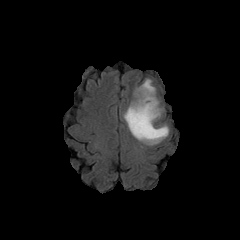

We introduce a neural network framework, utilizing adversarial learning to partition an image into two cuts, with one cut falling into a reference distribution provided by the user. This concept tackles the task of unsupervised anomaly segmentation, which has attracted increasing attention in recent years due to their broad applications in tasks with unlabelled data. This Adversarial-based Selective Cutting network (ASC-Net) bridges the two domains of cluster-based deep learning methods and adversarial-based anomaly/novelty detection algorithms. We evaluate this unsupervised learning model on BraTS brain tumor segmentation, LiTS liver lesion segmentation, and MS-SEG2015 segmentation tasks. Compared to existing methods like the AnoGAN family, our model demonstrates tremendous performance gains in unsupervised anomaly segmentation tasks. Although there is still room to further improve performance compared to supervised learning algorithms, the promising experimental results shed light on building an unsupervised learning algorithm using user-defined knowledge.